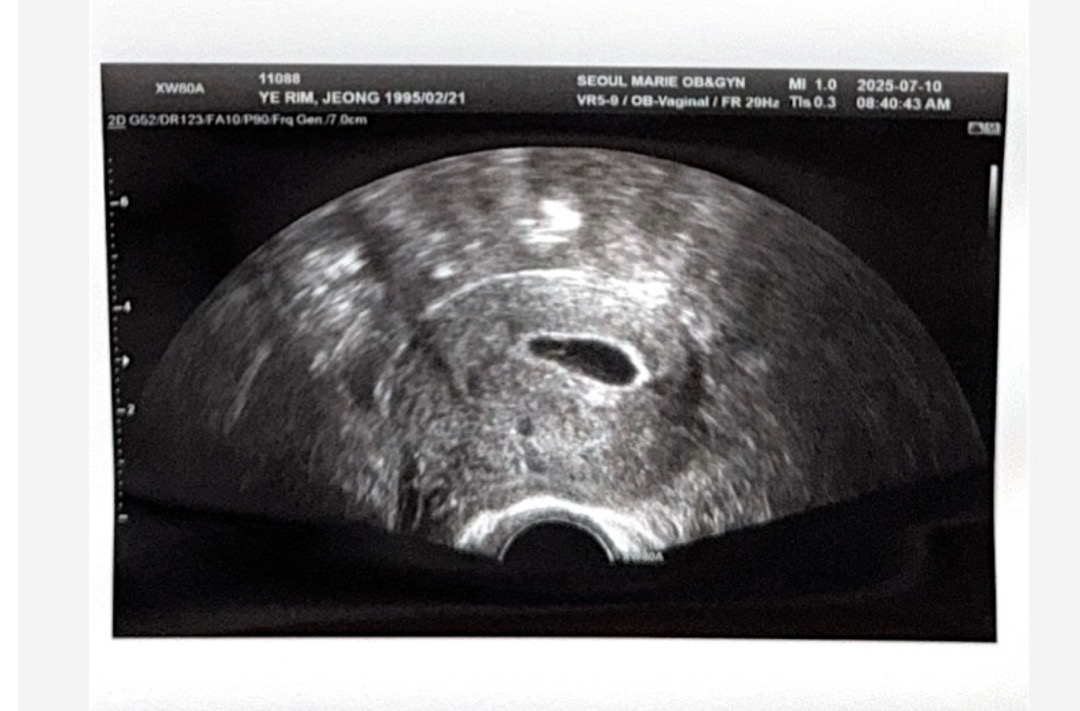

일주일만에 아기집이 이렇게 컸어요!😍

지금 가장 걱정 많은 시기인 우리잖아요😢 검색, 커뮤니티에 무한 노출되면서 안 좋은 이야기를 너무 많이 접하니까 맘이 너무 불안하더라구요. 그래서 우리 베동에는 좋은 이야기도 많이 많이 공유 되었으면 좋겠어요!! 4주 5일에 0.35 아기집 보고 5주 5일 오늘 이렇게 커졌어요 ! 난황이랑 아주 작은 아기, 심장 깜박임 보고 왔어요. 특히 저는 생리통처럼 배가 많이 아팠는데 아기집 크느라 그랬나봐요. 입덧, 배앓이 고생하고 있는 우리 모두 아기가 크는구나~ 하고 긍정적인 생각으로 내년 3월에 건강하게 출산했으면 좋겠어요🙏🏻